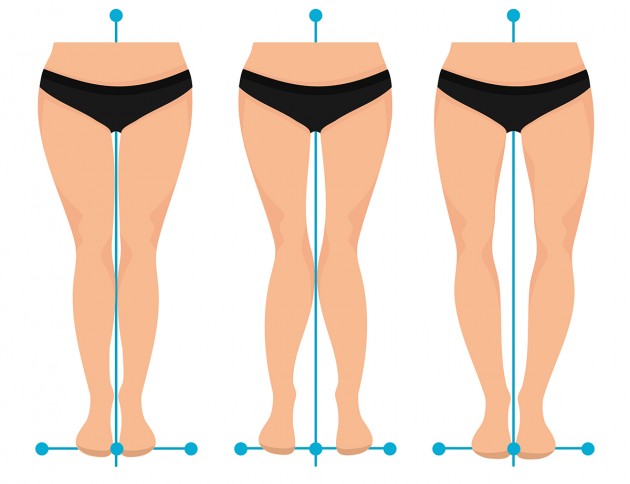

Orteza została stworzona z myślą o pacjentach z koślawością i szpotawością kolan.

Orteza została stworzona z myślą o pacjentach z koślawością i szpotawością kolan.

- osteoartroza stawu kolanowego koślawość lub szpotawość stawu kolanowego,